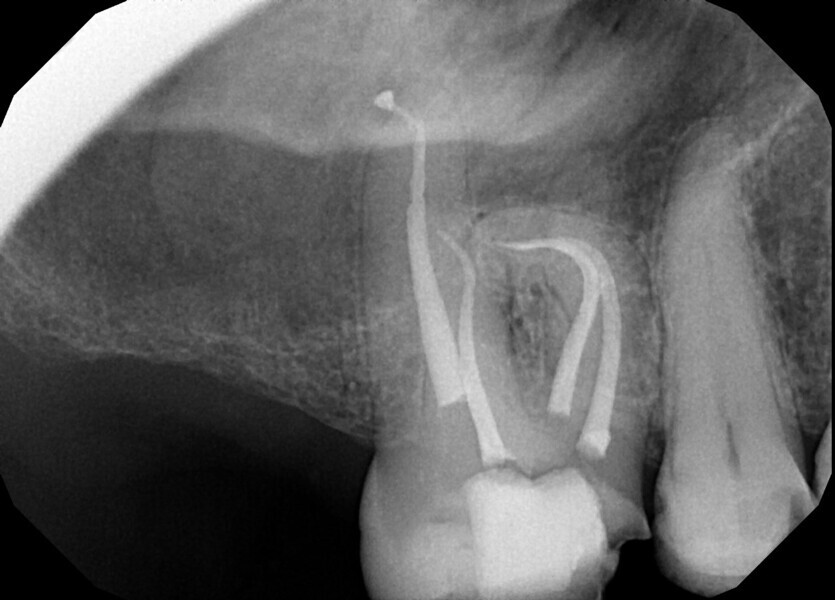

Fig. 14a: Case treated with Bassi Logic controlled memory nickel titanium files. Note the visualization of the third root on this lower molar and conservative canal preparation shape. (Courtesy of Dr. Alex Chan)

Fig. 14b: Case treated with Bassi Logic controlled memory nickel titanium files. Note the visualization of the third root on this lower molar and conservative canal preparation shape. (Courtesy of Dr. Alex Chan)